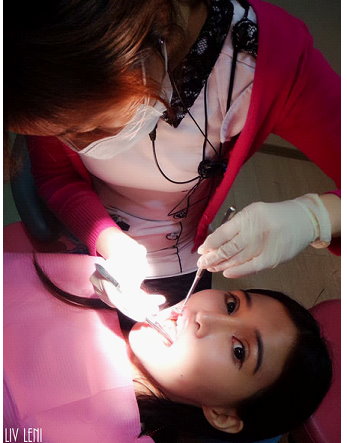

所有治療前都必須透過 牙周囊袋測量,

來判別牙周受破壞的程度、以及需要何種治療,

醫師會先拿一根 牙周探測器,插入牙齦溝測量深度,

健康時,牙齦溝的深度大約1~3釐米,

大於3釐米就表示已形成囊袋,越深代表牙周破壞越嚴重。

打上麻藥後,開始進行 右邊口腔的牙周刮除術,

雖然看器械好像很可怕,

但因為麻藥的關係,過程中是沒有感覺的,而且相當快速。

(圖中醫師正拿著牙周探測器,測量我的牙周囊袋。)

這個步驟是醫師拿牙周探測器,

測量經過刮除治療與正確刷牙後,牙周囊袋有無改善。